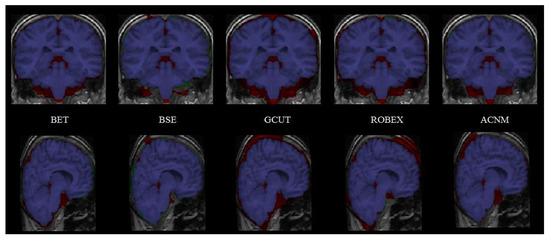

4. Discussion